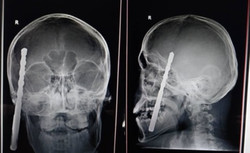

13:24, 25 Июль 2023

Башына бурагыч кирип кетип, аман калган ооматтуу жигит. Нейрохирургдун баяны